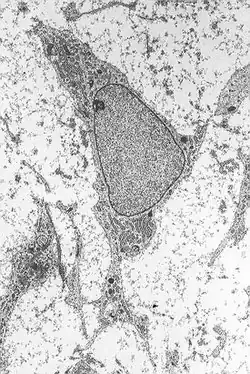

The proposed method involved converting mesenchymal stem cells—normally destined to become bone or adipose tissue—into neurons through brief exposure to retinoic acid diluted in ethanol.[15] The procedure consisted of extracting cells from the patient's bone marrow, exposing them in vitro to an 18 micromolar solution of retinoic acid for two hours, and subsequently reinfusing them into the same patient.[16]

The rejection was based on several issues: the application lacked sufficient methodological details, it claimed a cell differentiation process that was deemed implausible given the extremely short incubation time (between 40 minutes and 2 hours), and the observed morphology of the supposed nerve cells could have resulted from cytotoxic effects rather than genuine differentiation.[16]